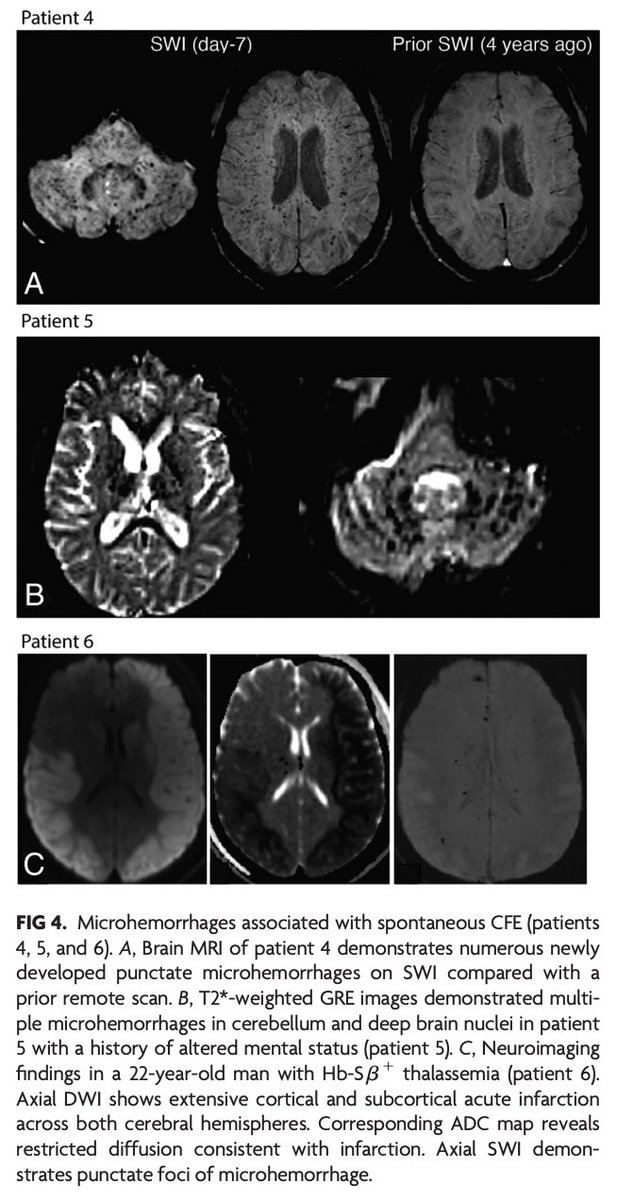

@Rshnzr @HosseiniHelia @zack4186 "CFE in sickle cell–related hemoglobinopathies is more common in complex hemoglobinopathies with otherwise milder disease course and is typically more fulminant compared with traumatic CFE. MRI findings follow a pattern with scattered foci of restricted diffusion, known as the

"Nontrauma-Associated Cerebral Fat Embolism Syndrome in Sickle Cell–Related Hemoglobinopathies: A Case Series and Systematic Review" https://t.co/mjcZ5AQXte

#FellowsJournalClub

@Rshnzr; @HosseiniHelia; @zack4186